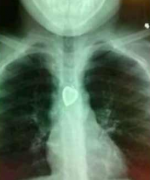

Laci Davis, an 8-year-old in Cincinnati, Ohio, accidentally ingested her necklace and heart-shaped locket, which lodged in her throat.

The pothole dislodged the locket, which then dropped down into Laci's stomach. The pain was gone, and Laci could breathe normally.

Doctors told Laci the locket will come back out "the old-fashioned way." Laci says she'll get a new locket instead retrieving this one. http://www.kptv.com/story/16018828/pot-hole-saves-girls-life -via Fark

(Image source: WCPO/CNN)